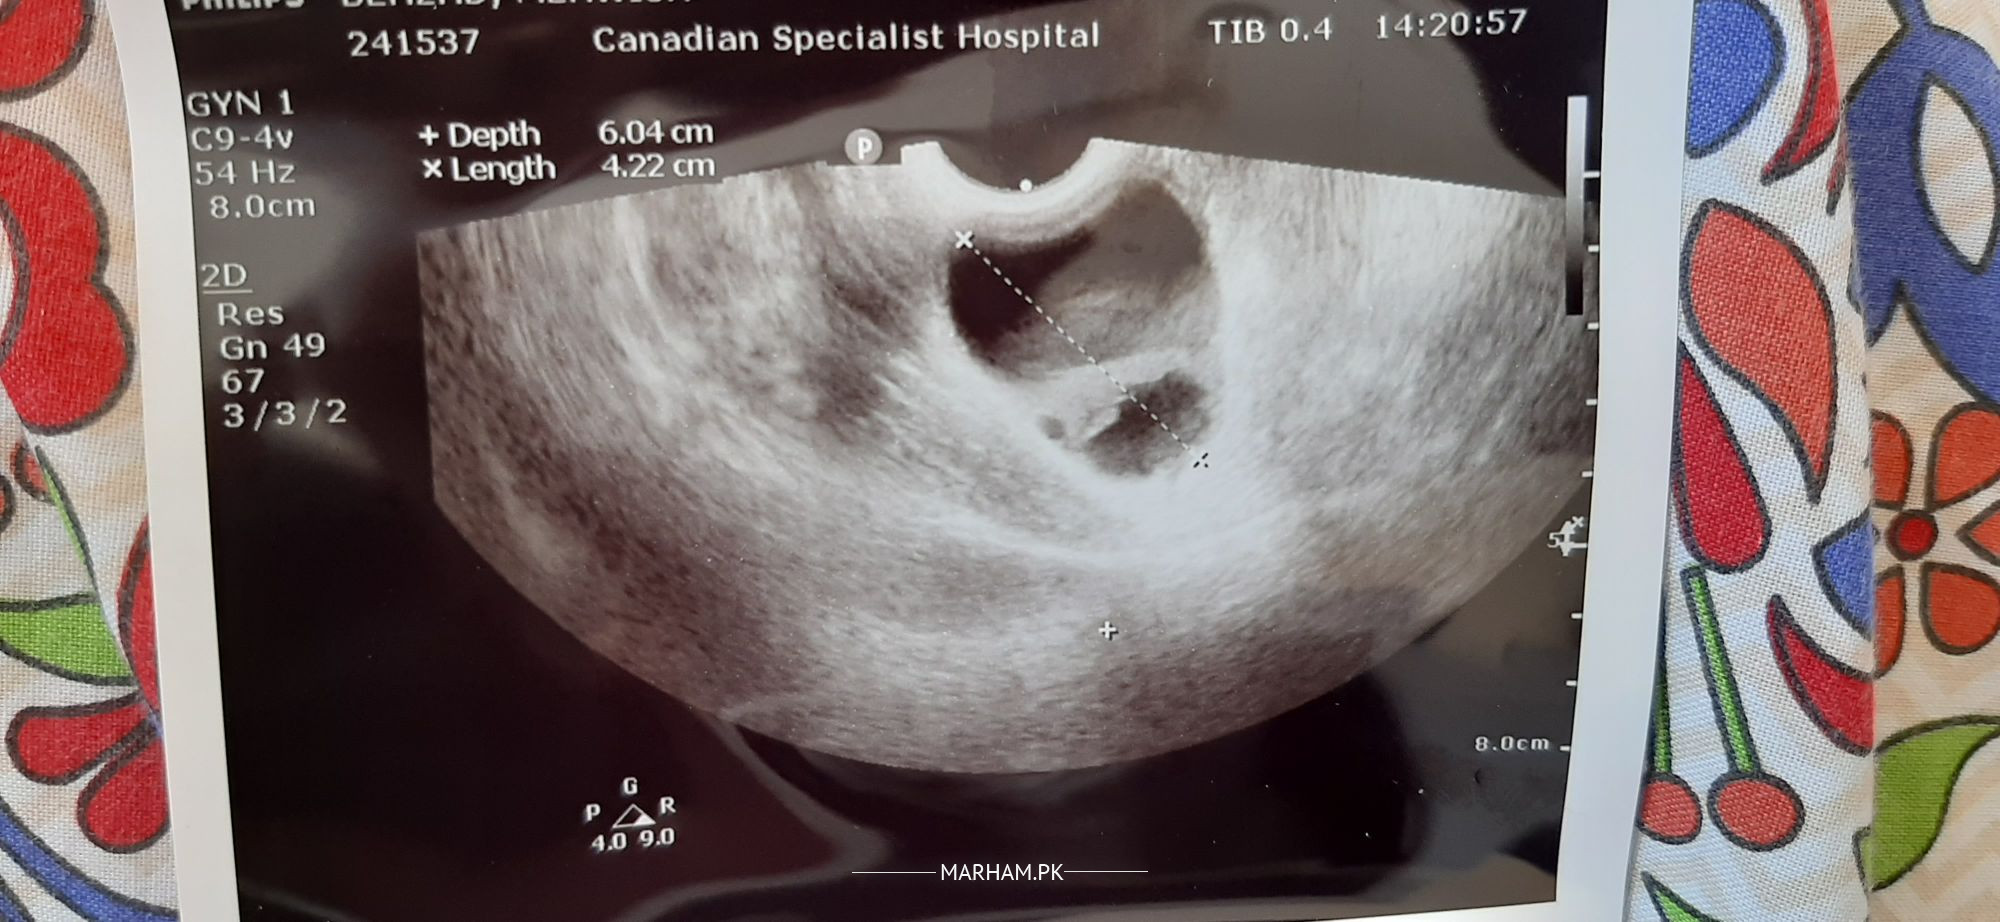

i am 6weeks and 2 days pregnant. i am sharing my 5 week 4 days sonography. Doctor said come again after 2 weeks. plz explain this sonography. everything is normal? Also have ovarian cyst in right side.

This is normal sonography there is no ovarian cyst that ovary is supplying food to the embryo that is why enlarged that is also normal after 12 week placenta will take over this function no worry BT relax and then have another ultrasound at 16 week